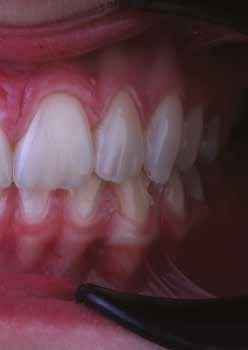

Egy 30 éves, negatív kórtörténettel rendelkező beteg azzal a kéréssel fordult hozzánk, hogy cseréljük ki az UR1 traumája után, 10 évvel korábban készült korábbi kompozit-helyreállítást.

A klinikai vizsgálat során az UR1 reagál a viabilitási tesztre, és az ugyanazon a napon készült röntgenfelvételen nem mutat periapikális elváltozásokat (1. ábra).

Az UR1 elszíneződött, és palatálisabb helyzetben van, mint az ellenoldali központi UL1 (2. ábra)

Az esztétikai elemzés a gingivális zenit aszimmetriáját mutatja az UR1 és az UL1 között. Parodontális szonda segítségével, plexusérzéstelenítés után, az IA

típusú funkcionális hám megváltozott passzív erupcióját igazoljuk Coslet és mtsai. osztályozása szerint (3. ábra)

A lehető legkonzervatívabb helyreállító kezelés elvégzése érdekében a páciensnél, figyelembe véve a megtartott fogelem korát és vitalitását, a tervezés és a diagnosztikai felviaszolás után a közvetlen kompozit-helyreállítás elvégzése mellett döntünk.